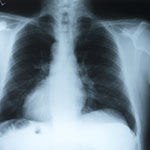

נזקי העישון הם רבים וגורמים במצבים הקלים לבעיות אסתטיות ובמקרים הקשים למחלות סרטן ריאות ולמחלת COPD. ד"ר יהודה שוורץ, מומחה למחלות ריאות, מסביר כיצד ניתן לטפל במחלה שניתן למנוע ומתריע: הפסיקו לעשן וגשו לבדיקת תפקודי ריאה